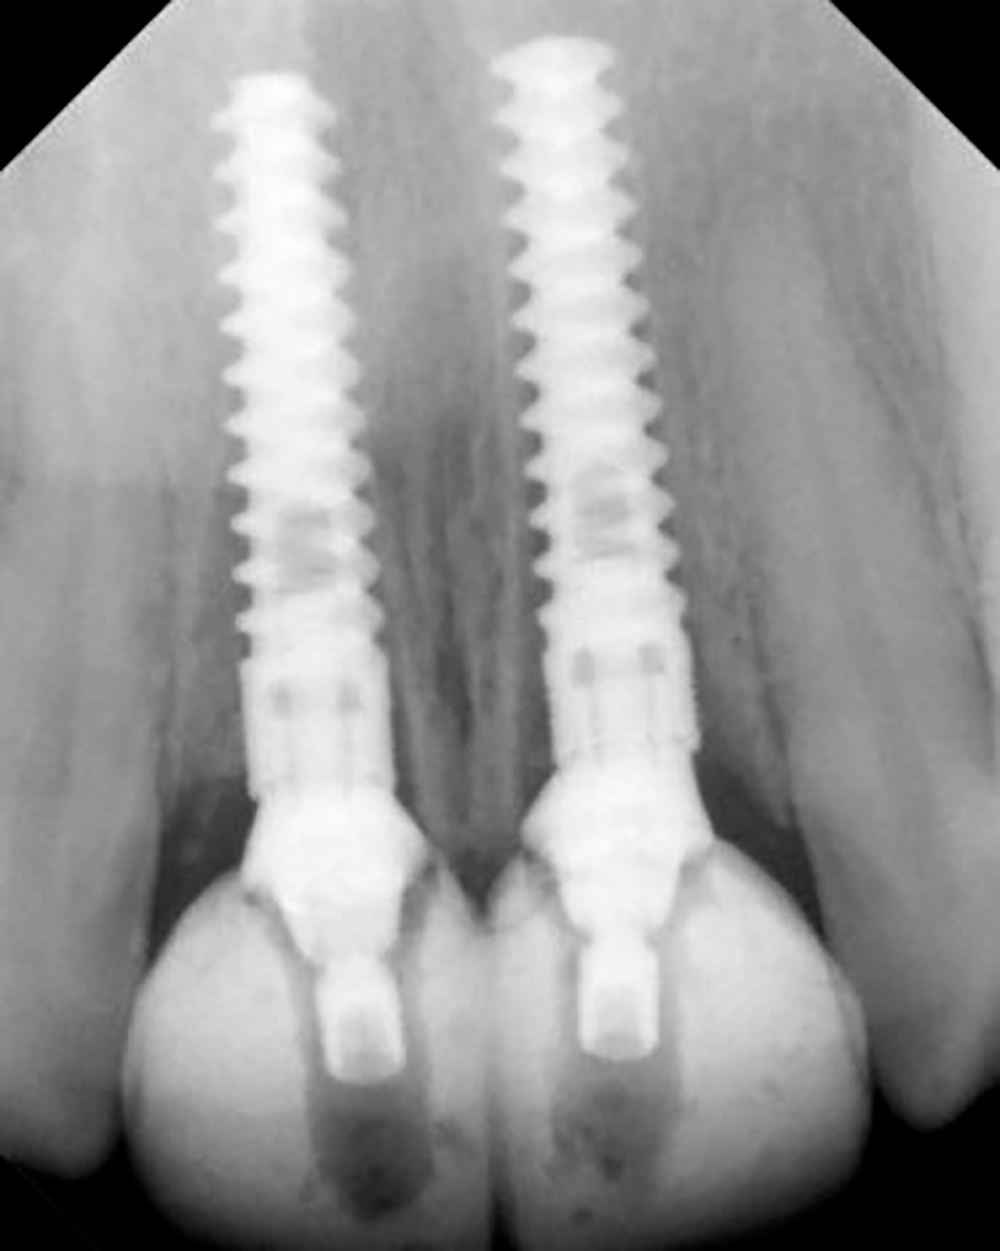

X-Ray after placement